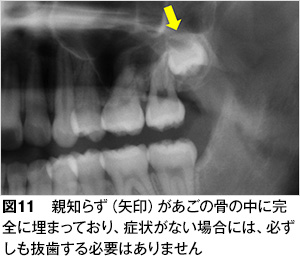

| 2. | 顎の骨の中に完全に埋まっていて問題が無い:写真(図11)は、親知らずが顎の骨の中に完全に埋まっている状態です。この親知らずは周りの歯や骨に悪い影響を与えることはないと考えられ、痛みや腫れなどの症状がなければ直ちに抜く必要はありません。 |